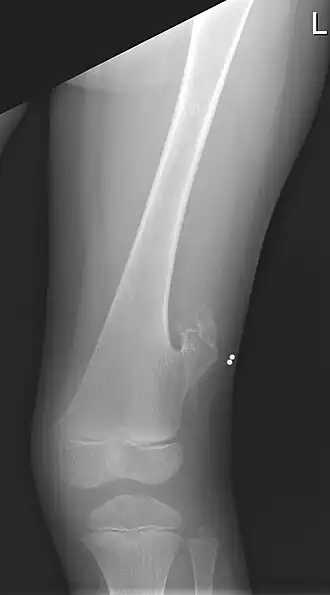

L'exostose est le développement d'un ostéochondrome, une excroissance osseuse bien différenciée qui conduit au développement d'un nouvel os à la surface d'un os. Elle peut être causée par un traumatisme comme un choc, une inflammation ou être d'origine héréditaire. Produite par une coiffe de cartilage germinatif pendant la croissance, c'est la tumeur osseuse bénigne la plus fréquente[1].

L'ostéochondrome est un excroissance osseuse bien identifiable mais disposée en continuité parfaite avec l'os porteur. Elle peut toutefois inclure des résidus cartilagineux plus ou moins calcifiés[1].